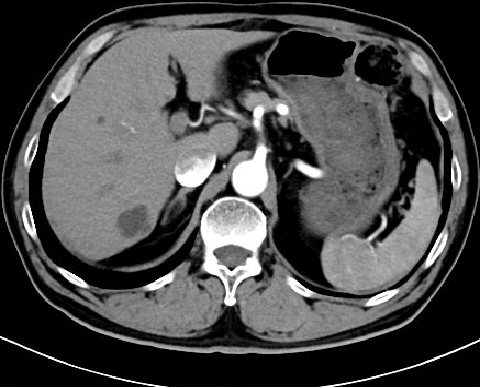

2018.07.20:

2018.10.08:

2018.10.10 瑞戈非尼

80-120-160 qd 21/28

影像学评价:PD

2019.03.07: